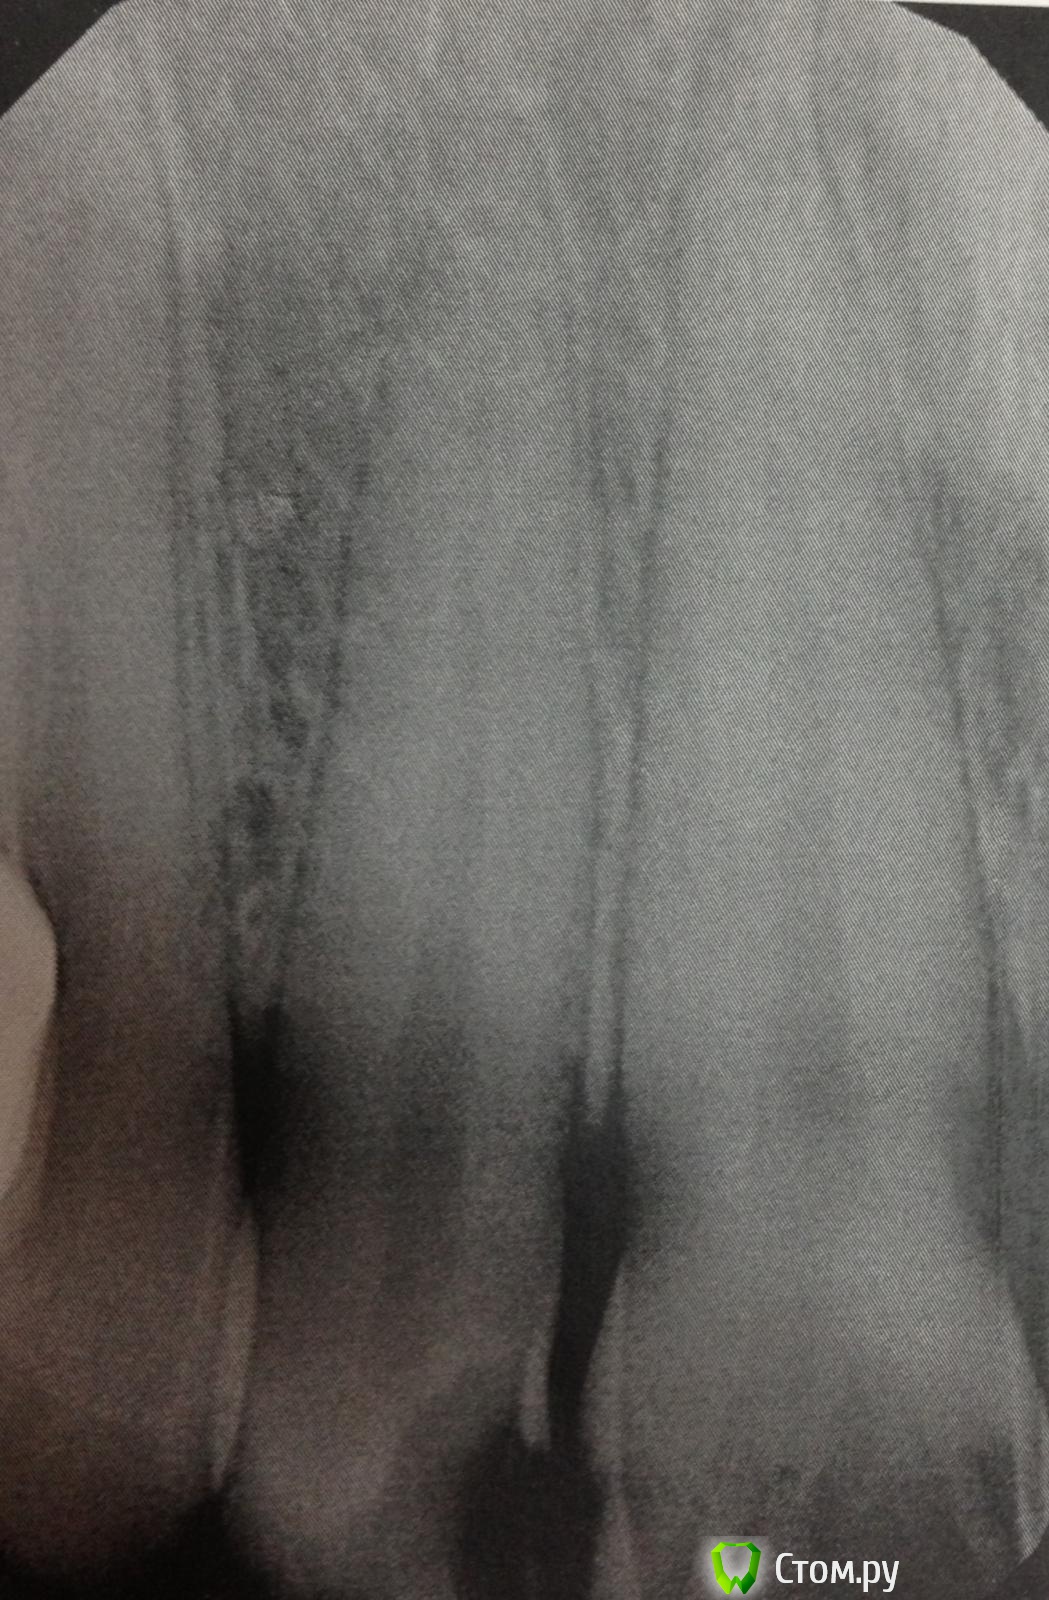

SSTi Опубликовано 6 сентября, 2014 Автор Поделиться Опубликовано 6 сентября, 2014 (изменено) Новая история.Пациент молодой.4 резца вч.12 периодонтит. 11 кариес дентина. 21, 22 - периодонтитСитуация до1 посещение. Анестезия 1.7 в области 21-22. Коффер. Преп. Обработка каналов. Ирригация. Кальций. Временная.2 посещение. Анестезия в области 11 ,12, 21 ,22. Коффер. Преп и реставрация 11.Преп, обработка и ирригация 12, паковка.Ирригация 21-22. При пошружении файла в каналы 21 и 22 - боль за 3-4 мм до апекса. Не кровит. Обработка была в пределах разумного(ленточное перфо не мог натереть). Идем на снимокБоль на этом уровне. Причем при введении мастер штифта боль есть. Если ввожу 15-20 аккуратно - боли нет. Добавляем анестезию. Аккуратно удается запломбировать 22.21 - боль осталась. Оставил кальций.На корнях 22 и 21 в боковом отделе есть разрежения небольшие. Боль примерно на их уровне. Но это вряд ли связано думаю. (Это латерали?).Вопрос. Какова причина боли? Склоняюсь к анестезии. Такое чувство, что повторно плохо взяла(посещения рядом по времени).+ слизистая вобл 21 была слабочувствительна Изменено 6 сентября, 2014 пользователем SSTi Ссылка на комментарий